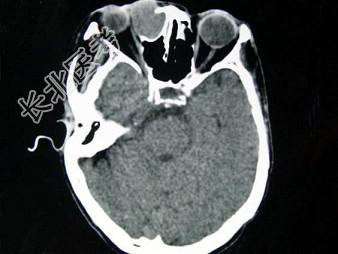

- 单项选择题女,40岁, 右眼反复溢泪伴眼球渐进性突出2年余,眼球运动受限, CT检查如图所示,最可能的诊断是 ( )